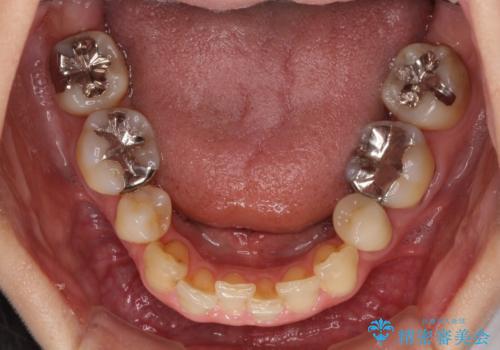

矯正の後戻りの改善と銀歯をセラミックに

- 上下前歯の叢生を気にして来院された患者様です。

費用を抑え、期間もあまりかけずに治療をしたいとのことで、インビザライン・ライトを用いて矯正治療を行うこととしました。

矯正治療後には、下顎臼歯の目立つ銀歯をセラミックインレーにて修復治療を行いました。